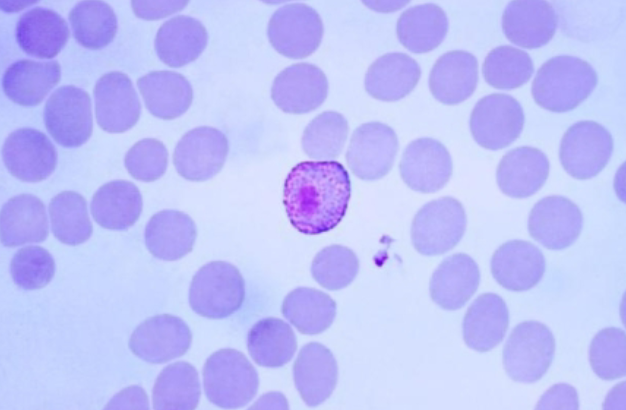

Plasmodium malariae

Plasmodium malariae